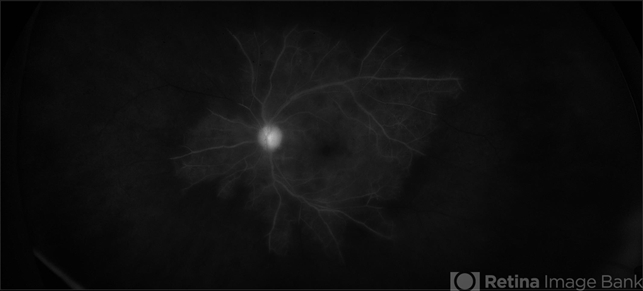

- proliferative diabetic retinopathy (PDR), diabetes, non-perfusion, capillary nonperfusion, neovascular glaucoma

- Fundus camera

- 68-year-old male with proliferative diabetic retinopathy, severe capillary nonperfusion and neovascular glaucoma. Treated with Avastin intra-ocular injection and future pan-retinal photocoagulation. VA 20/300.